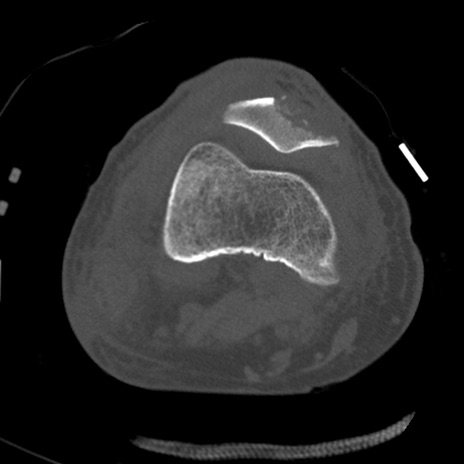

症例28 右膝関節CT(横断像)

右膝関節CT